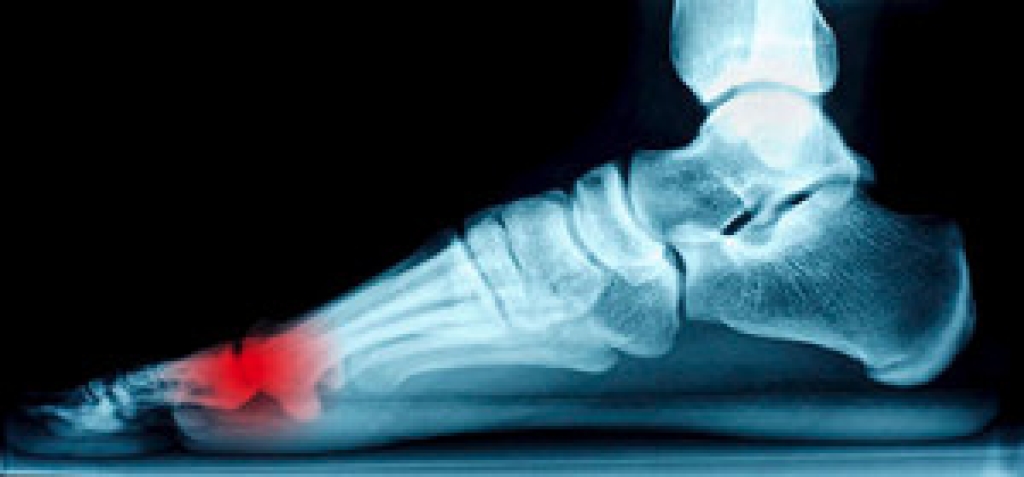

Causes of Sesamoiditis

- Sudden increase in activity

- Increase in physically strenuous movement without a proper warm up or build up

- Foot structure: those who have smaller, bonier feet or those with a high arch may be more susceptible

Treatment for sesamoiditis is non-invasive and simple. Doctors may recommend a strict rest period where the patient forgoes most physical activity. This will help give the patient time to heal their feet through limited activity. For serious cases, it is best to speak with your doctor to determine a treatment option that will help your specific needs.